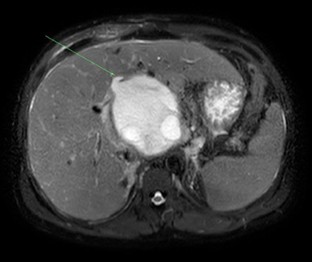

Fig. 1

Fig. 2

Fig. 3

Fig. 4